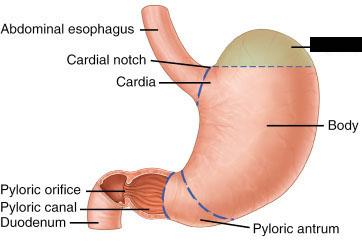

Body (of stomach)

Cardia (of stomach)

Duodenum

Fundus (of stomach)

Gastroesophageal sphincter

Pyloric Sphincter

Pylorus (of stomach)

Rugae (of stomach)